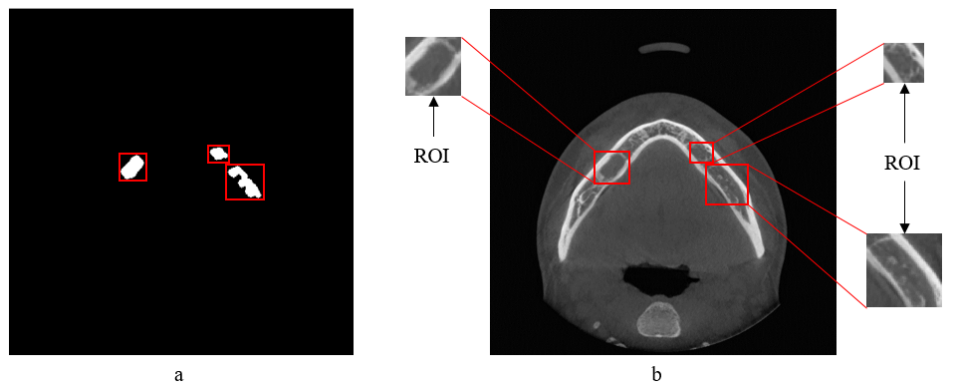

4.2.2 Feature extraction

The reason of feature extraction is to acquire sufficient information about an image. Once all the initial lesion candidates were detected, a bounding rectangle around each blob were calculated (Figure 4(a)). The rectangles were then superimposed over the intensity image in the same position relative to the detected blobs (Figure 4(b)). Then image sections inside each rectangle were cropped out for feature extraction and considered as Region of Interest (ROI).

Refer to caption

Figure 4: Illustration of ROI extraction process. (a) Bounding rectangles calculated around each blob, (b) Bounding rectangles were superimposed over the intensity image to crop out the ROIs.